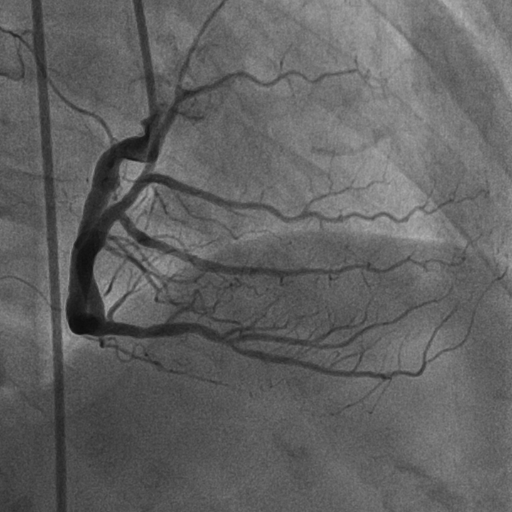

การตรวจประเมินหลอดเลือดหัวใจชนิดไม่รุกราน (Non Invasive) ได้รับความนิยมเพิ่มขึ้น ทั้งการทำ Stress Echocardiography, Stress Cardiac Magnetic Resonance Imaging (Stress MRI) และ Coronary Computed Tomographic Angiography (CCTA) ซึ่งสามารถคัดกรองผู้ป่วยที่มีผลการตรวจปกติหรือผิดปกติเพียงเล็กน้อยออกไป โดยไม่จำเป็นต้องไปถึง การฉีดสีสวนหัวใจ (Coronary Angiography: CAG) ซึ่งเป็นการตรวจชนิดรุกราน (Invasive) และมีภาวะแทรกซ้อนมากกว่า แต่ในกรณีที่ผลการตรวจผิดปกติชัดเจนมักจะนำไปสู่การฉีดสีสวนหัวใจ ซึ่งเป็นมาตรฐานในการวินิจฉัยโรคหลอดเลือดหัวใจ

ภาพการฉีดสีสวนหัวใจ (Coronary Angiography : CAG)